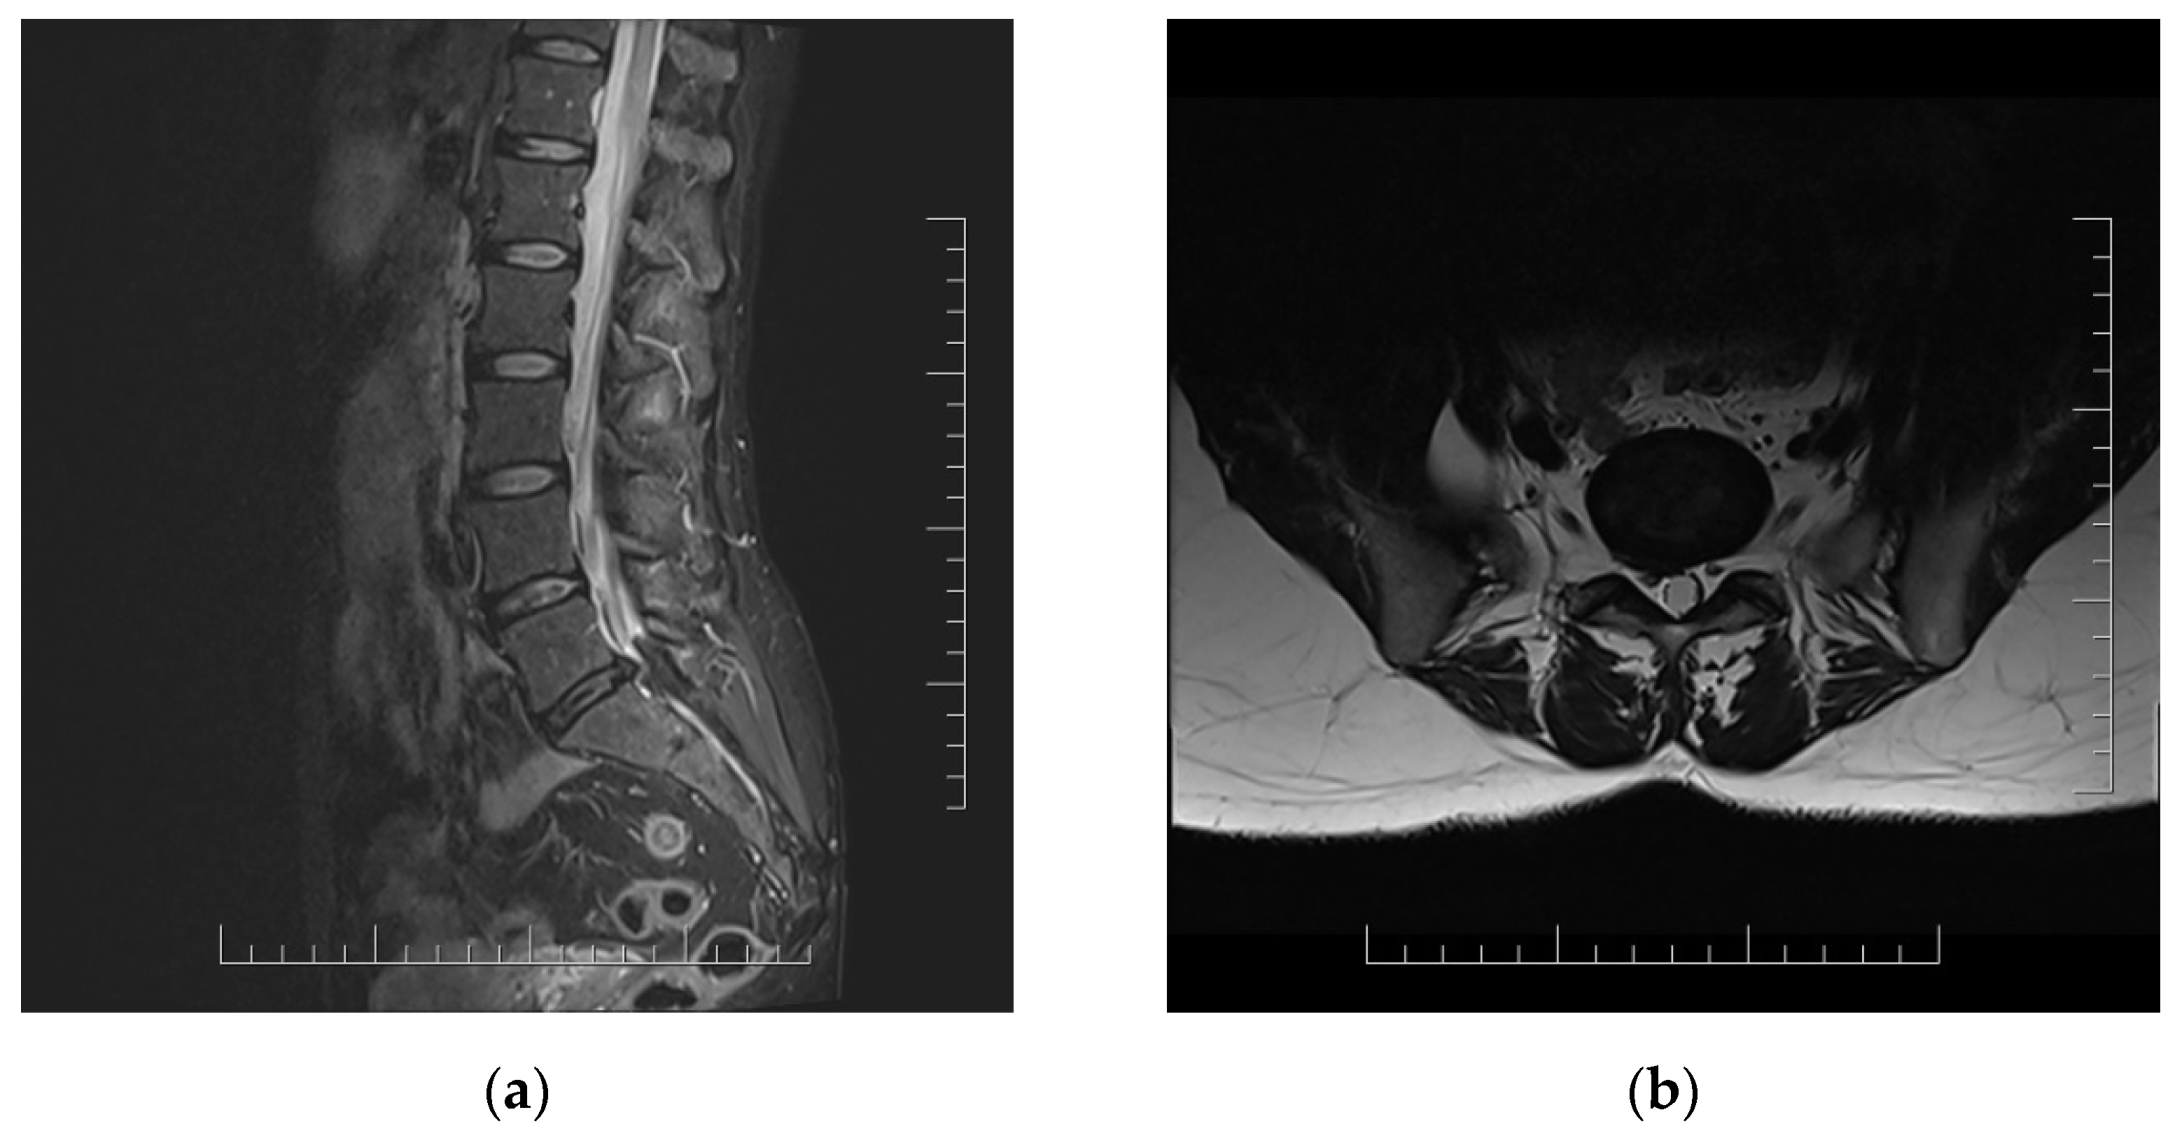

Lumbar MRI scans were performed twice (2 and 4 months after acute infection). Both MRI scans showed right disc herniation in level L5/S1 in correlation with clinical manifestations (Figure 1).

Figure 1.

MRI scans of lumbar spine in 51 year old woman with persistent lumbar pain and radicular irritation of right L5 and S1 in chronic long COVID with correlation with L5/S1 disc herniation. (a) Sagittal T2-weighted sequence; (b) axial T2-weighted sequence.